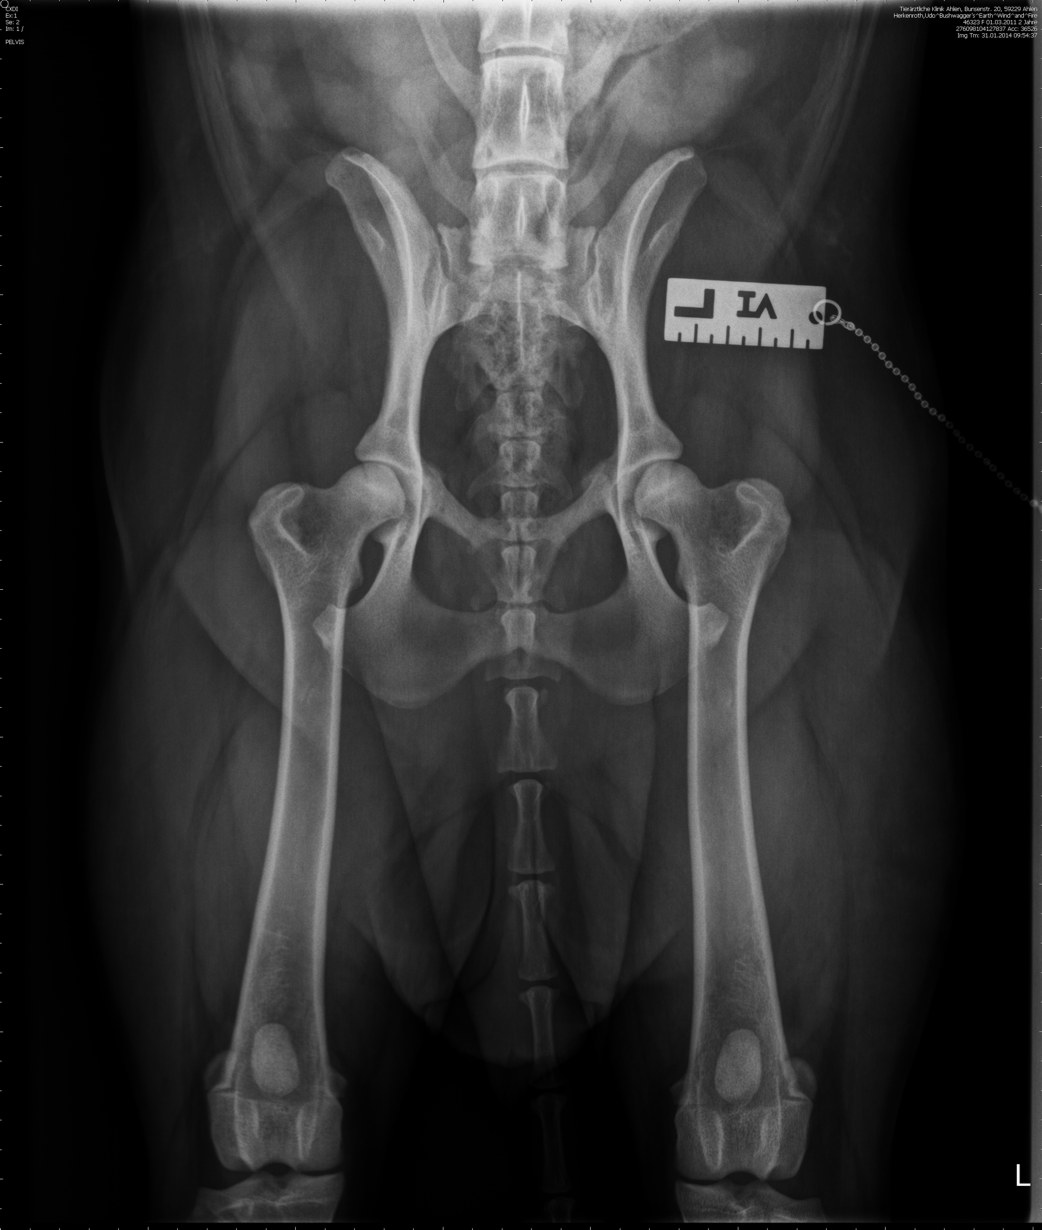

HD

(Röntgenbild)